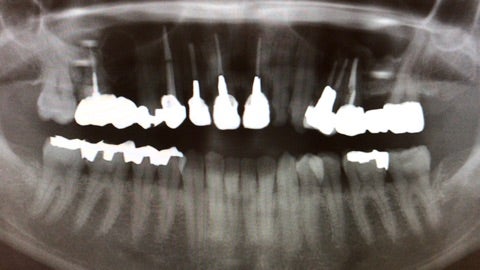

「数年前から右上の歯に違和感があり、かかりつけの歯医者で歯の治療を繰り返していたが違和感が消えない。」

▶︎それよりも私がまず気になったのは赤いラインで引いた丸い透過像でした。続いて精査するためにCT撮影を行いました。